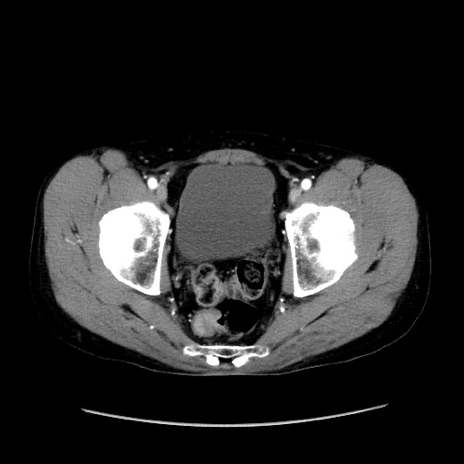

症例37(横断像)

【症例】40歳代 男性

【主訴】腹痛

【現病歴】4時間ほど前に電車に乗車中に臍部上より腹痛出現。徐々に増悪し起立困難となり、救急外来受診。生ものは数日食べていない。今朝お雑煮を食べた。

【身体所見】BT 36.8℃、BP 117/84mmHg、HR 91/min、SpO2 97%、苦悶様、腹部:臍上部広範囲圧痛あり、反跳痛±

【データ】WBC 8100、CRP 0.03